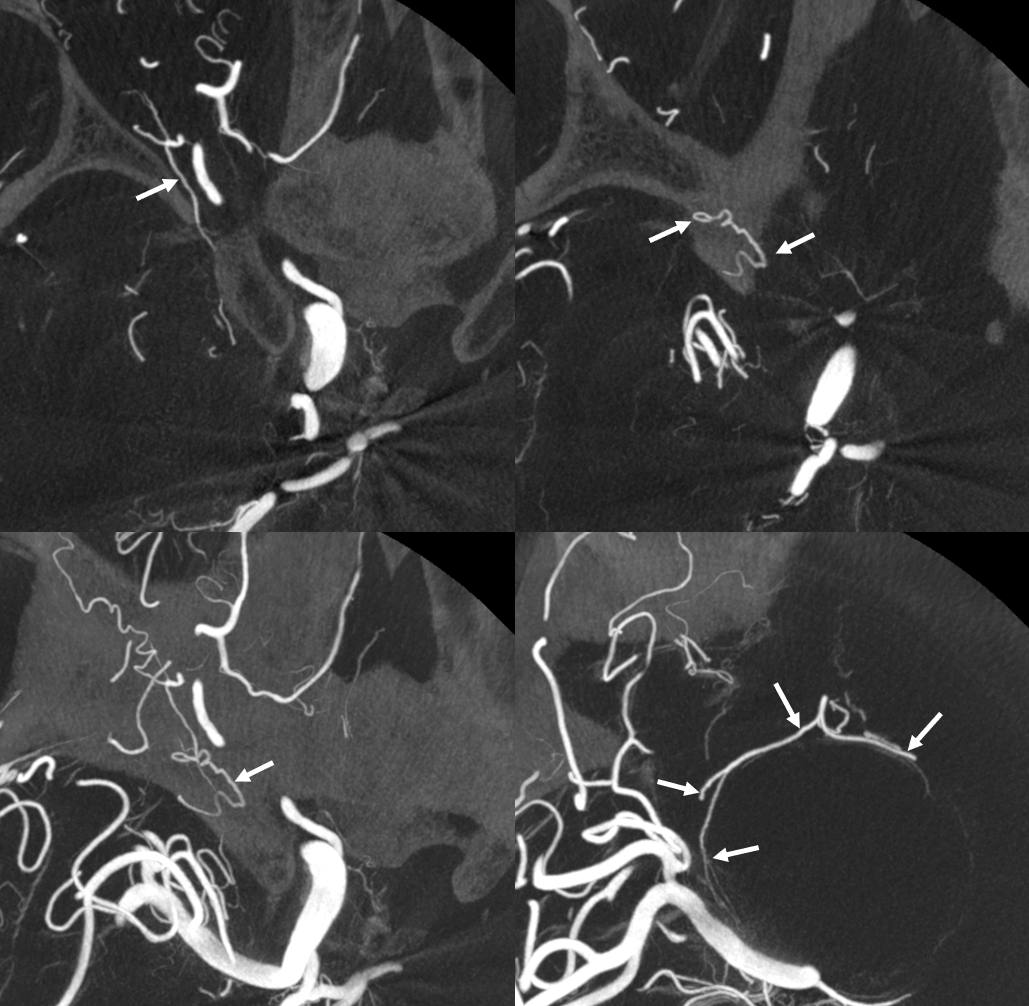

Cone Beam CT

With arrows — vasa vasorum are curiously dural in origin here — via deep recurrent meningeal (dashed arrows). Solid arrows are surface vasa vasorum

Sagittal MIPS show hazy eggshell wall enhancement